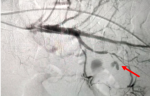

Follow-up and outcome of intervention: on the fifth day of treatment, the patient experienced a severe complication in the form of massive hematochezia, prompting an urgent interventional response. A subsequent angiography procedure was performed, which identified the source of the hemorrhage as a pseudoaneurysm of the biceco-appendicular artery, a branch of the superior mesenteric artery (Figure 1); this life-threatening lesion was then successfully treated via endovascular embolization using four Vortex 0.18 coils, each with a diameter of 3mm (Figure 2).

Figure 1: diagnostic arteriography image showing the pseudoaneurysm (false aneurysm) on the biceco-appendicular artery